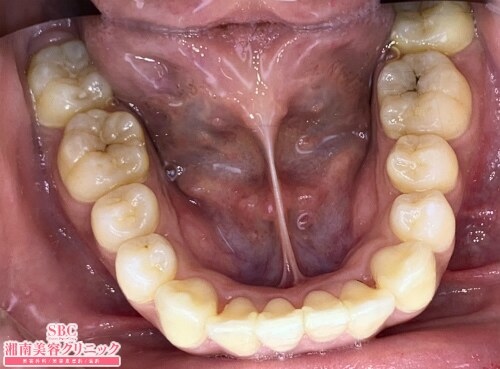

山元亮士(歯科) 医師

施術前

施術後8ヶ月後

.・歯を極力削りたくない方・ワイヤーは嫌な方・審美目的の神経治療に強く抵抗がある方・矯正中のことを周りにバレたくない方・前歯だけ少し動かしたい方.インビザラインGO・2019年、2020年、症例数日本一ご自身で着脱できるので歯磨きしやすく、お口の中を衛生的に保てます。食事中はマウスピースを外すので、食べにくいといった不快感もゼロですワイヤーがないので、口の中が傷付きにくい。.リスク:IPR(歯間を削る事)する場合、冷水痛顎関節症、後戻りetc 施術の説明:マウスピース矯正は、1日20時間以上マウスピースを装着する事により歯並びの矯正を行う事が出来る治療です。施術の副作用(リスク):歯を少し削る事があります。アタッチメントと呼ばれる装置を歯に取り付ける必要があります。後戻りの可能性があります。計画通りに歯が動かない場合もあります。

インビザラインGO

・2019年、2020年、症例数日本一

ご自身で着脱できるので歯磨きしやすく、お口の中を衛生的に保てます。食事中はマウスピースを外すので、食べにくいといった不快感もゼロです

ワイヤーがないので、口の中が傷付きにくい。

施術の説明:マウスピース矯正は、1日20時間以上マウスピースを装着する事により歯並びの矯正を行う事が出来る治療です。

施術の副作用(リスク):歯を少し削る事があります。アタッチメントと呼ばれる装置を歯に取り付ける必要があります。後戻りの可能性があります。計画通りに歯が動かない場合もあります。